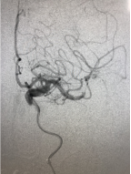

病例2

DSA显示左侧M2上干闭塞

微导管造影显示真腔

取栓后血管再通